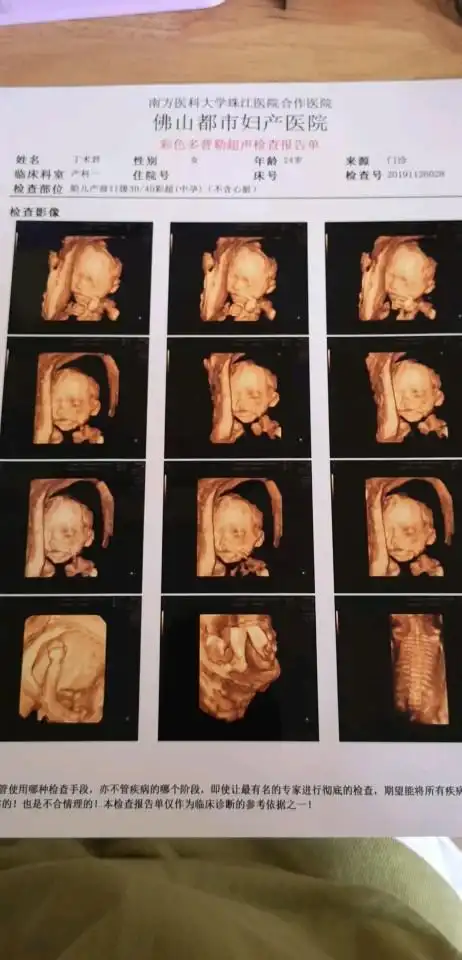

今天去查了,有小唧唧男孩,做四维医生说,脸像我,身高像我老公肯定好